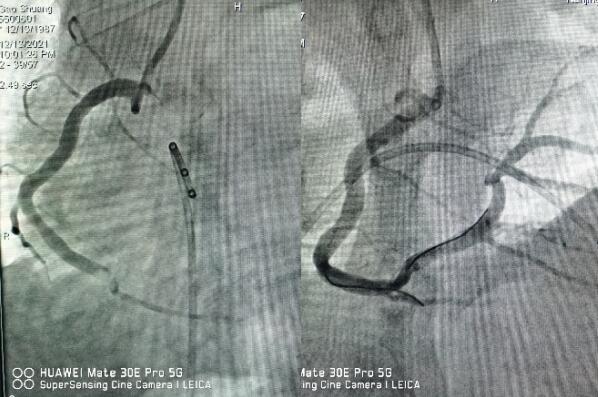

12月13日晚7點(diǎn)左右,一名32歲徐州在寧務(wù)工的男性患者,“突發(fā)胸痛1小時(shí)”來(lái)江寧中醫(yī)院就診,當(dāng)班醫(yī)師觀察到患者一般狀態(tài)極差,面色蒼白、大汗,

立即送入搶救室,測(cè)血壓92/60mmHg,心電圖提示急性下壁心肌梗死,三度房室傳導(dǎo)阻滯。

醫(yī)生立即予以搶救,并第一時(shí)間通知心內(nèi)科值班醫(yī)師,緊急啟動(dòng)綠色通道,全院相關(guān)科室全力配合,心內(nèi)科介入團(tuán)隊(duì)分工明確,迅速啟動(dòng)導(dǎo)管室。因患者心梗后并發(fā)嚴(yán)重心律失常,為了安全起見(jiàn),造影前植入臨時(shí)起搏器,造影提示右冠狀動(dòng)脈急性完全閉塞,并成功開通血管,患者胸痛即刻緩解,目前正在康復(fù)過(guò)程中。